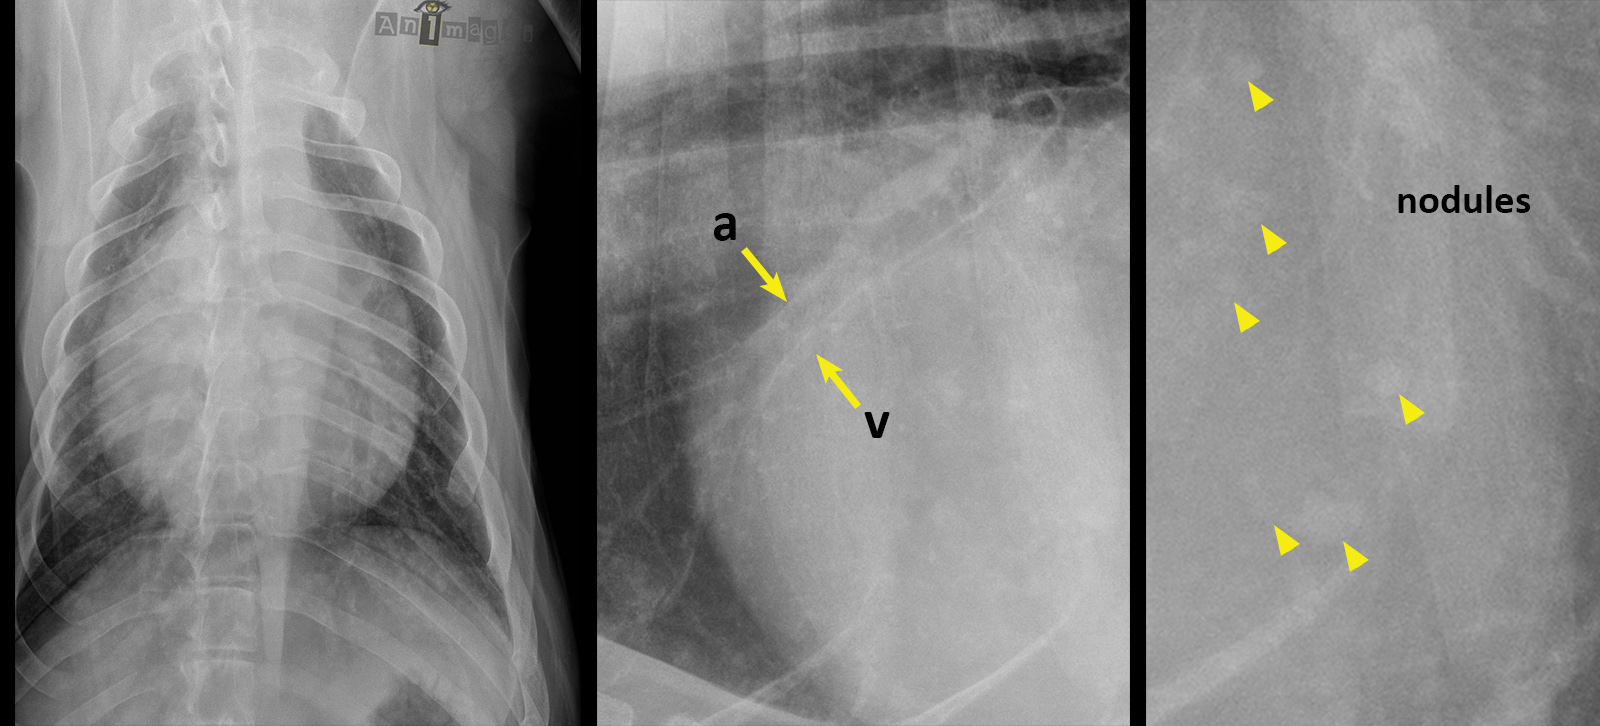

Oscar était mal en point… 54,2% d’entres vous aviez vu juste au moment d’écrire ces lignes. L’aspect globuleux de la silhouette cardiaque était bien suggestive d’épanchement péricardique. La petitesse des artères (a) et veines (v) pulmonaires crâniales appuyaient aussi une hypothèse de tamponade cardiaque davantage que celle d’une insuffisance cardiaque congestive. Et pour finir, de multiples opacités de tissus mous plus ou moins circulaires étaient présentes, suggérant fortement des métastases. Celles-ci étaient peut-être plus difficiles à percevoir sur vos écrans (seulement 2,3% d’entres vous en ont fait état… mais peut-être ne saviez-vous pas que vous pouviez sélectionner plusieurs signes radiographiques dans la liste ?).